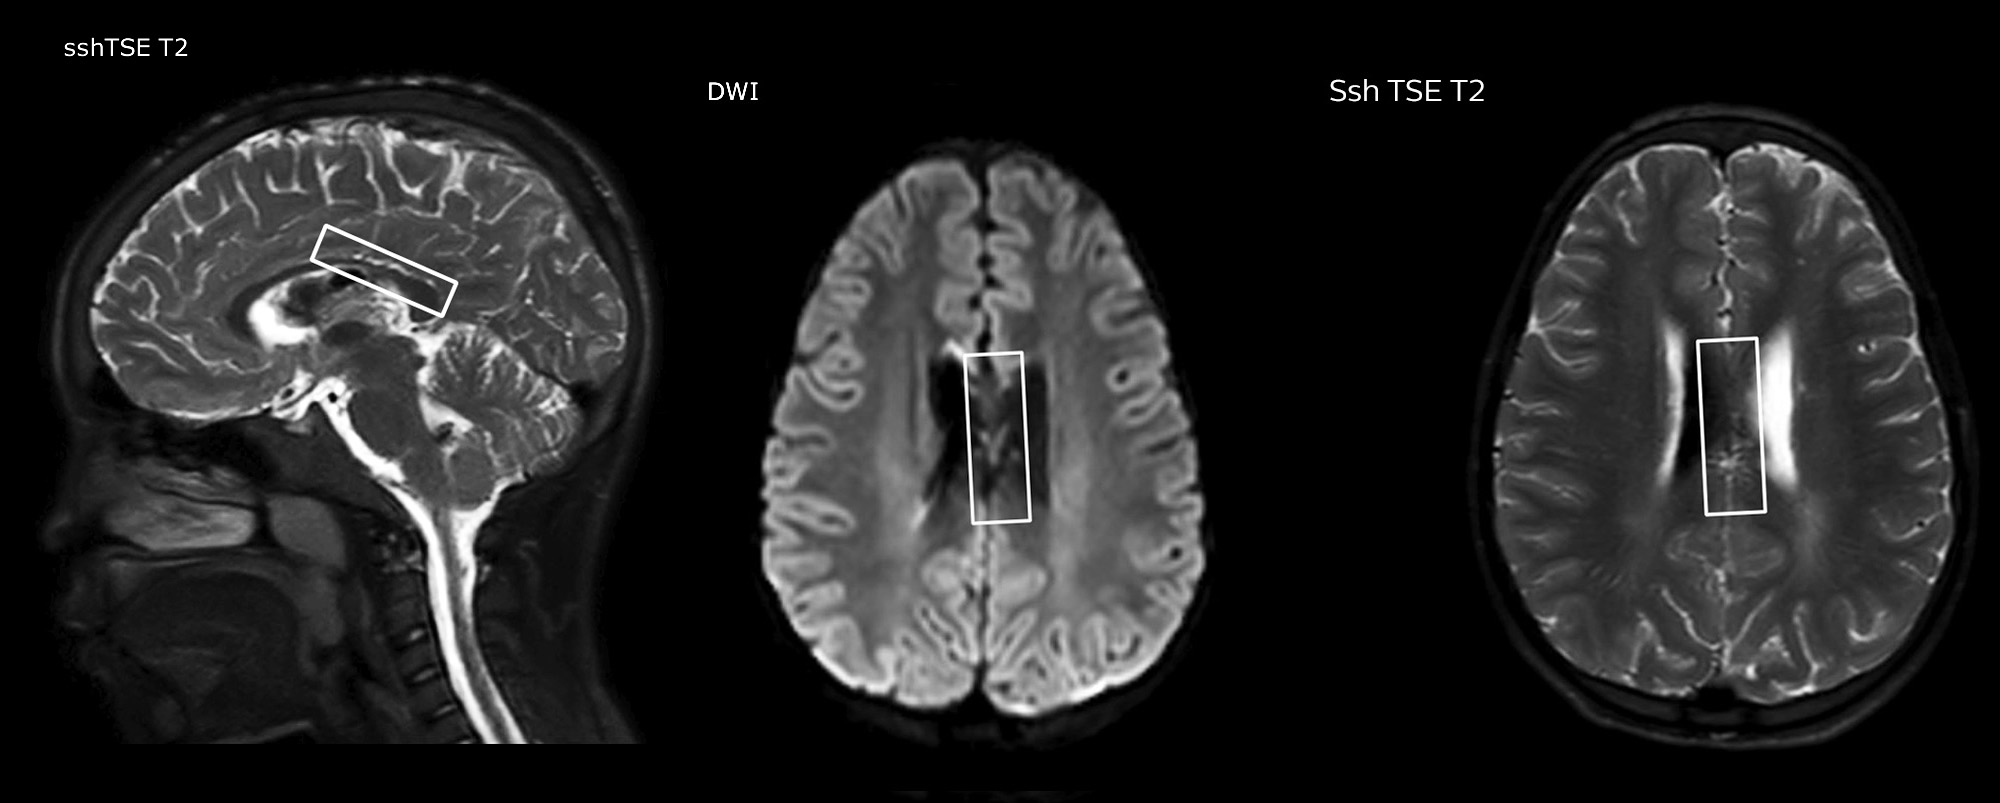

Pseudo-continuous arterial spin labeling (pCASL) was developed for brain perfusion imaging without contrast agent. “This is very desirable in pediatric patients where the general trend is to limit the administration of contrast,” says Dr. Miller. Growing confidence in specific applications “We built up confidence in pCASL by comparing it to contrast-based perfusion imaging. Once we had confidence that it was representing what the contrast perfusions were representing, we increased our diagnostic confidence by serial imaging in either the acute stage or the long term stages in a number of patients with arterial abnormalities.

Dr. Miller uses pCASL for all patients who present with chronic and acute cerebrovascular abnormalities such as acute stroke, as well as patients who present with signs of acute inflammation in the brain, and occasionally in patients with tumors, to assess the perfusion status of their tumor.

“In combination with diffusion weighted imaging, it can help give a more extended assessment of the degree of perfusion abnormality in a patient who is suffering acute ischemia. We have a number of patients who have chronic arterial insufficiency due to prior arterial abnormalities or acquired arterial abnormalities such as sickle cell disease or neurofibromatosis. Sometimes the child’s first manifestation of disease progression is a reduction in brain perfusion before stroke symptoms manifest clinically or in diffusion weighted imaging. We use pCASL to help delineate the perfusion abnormality.”